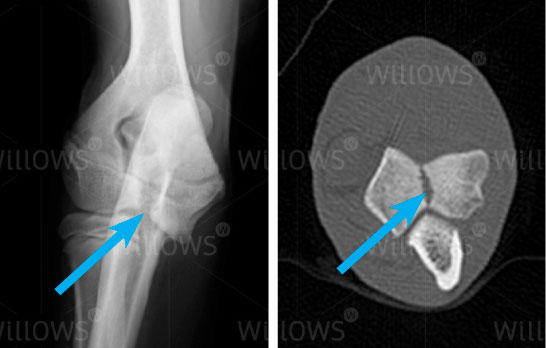

Fig 1: X-ray showing a humeral condylar fissure (arrow)

Fig 2: CT scan showing a humeral condylar fissure (arrow)

Examination of your pet will generally identify elbow pain and often show reduced muscle in the affected leg. Large fissures or cracks within the humeral condyle can be detected on X-rays, however incomplete or subtle fissures can often only be diagnosed on a CT scan. Because humeral condylar fissures often affect both front legs, a CT scan both elbows is usually recommended.